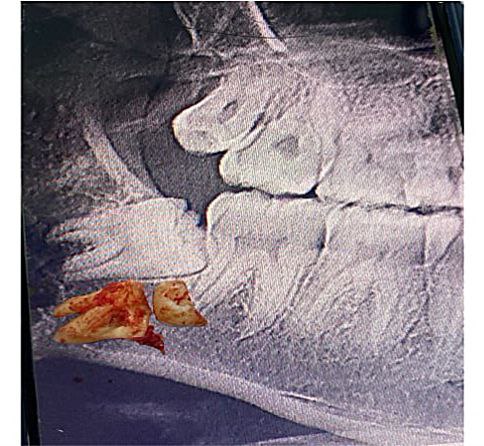

أجراء عملية قلع سن العقل لمريض في عيادة جراحة الفم

9 Nov

2022/11/09 اقرأ المزيد